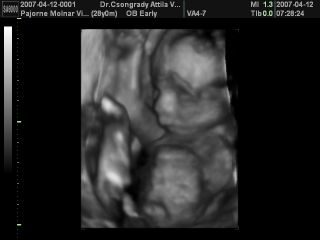

Megjöttem Uh-ról. Először a doki azt mondta, hogy kisfiú, aztán megvátoztatta kislányra. Utána meg is mutatta a nagyajkakat, és 100 %-ra állítja, hogy kislány.

Mutatok róla képeket.

Kép

Eléggé le kellett kicsinyíteni ahhoz, hogy fel tudjam tenni, nem tudom mennyire látszik.